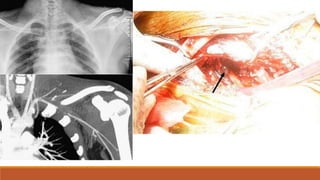

CT scan demonstrates an anterior mediastinal hematoma with a preserved fat plane between the

hematoma and the aorta. Arrow indicates a sternal fracture.